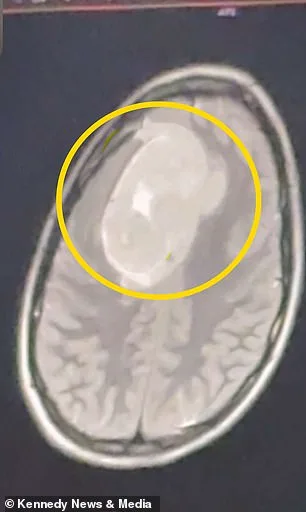

The first doctor she saw in December 2025 told her it was 'probably stress headaches.' A second doctor, during a Christmas break visit, finally ordered an MRI. The results were damning: a benign tumor, but one that was pressing on her frontal cortex, the part of the brain responsible for executive function, motor control, and language. 'I was stunned. That was the last thing that I would have expected,' Keating said. But why did it take months—possibly years—for the tumor to be detected? What protocols are in place to ensure that symptoms like hers don't slip through the cracks of a system that often prioritizes efficiency over accuracy?

The tumor, growing slowly over three to four years, was a silent saboteur. It was not a cancerous menace, but a quiet invader, one that could have altered her personality, cognition, and motor function if left untreated. 'I was scared and worried about the surgery,' Keating admitted. 'I didn't know coming out of it how I would act... or if there would be neurological effects.' The surgery, a six-hour craniotomy, was a necessary evil. Yet it begs the question: What if the government had mandated earlier screenings for young adults, or if regulations required doctors to consider rare but serious conditions before defaulting to 'stress' as a diagnosis?